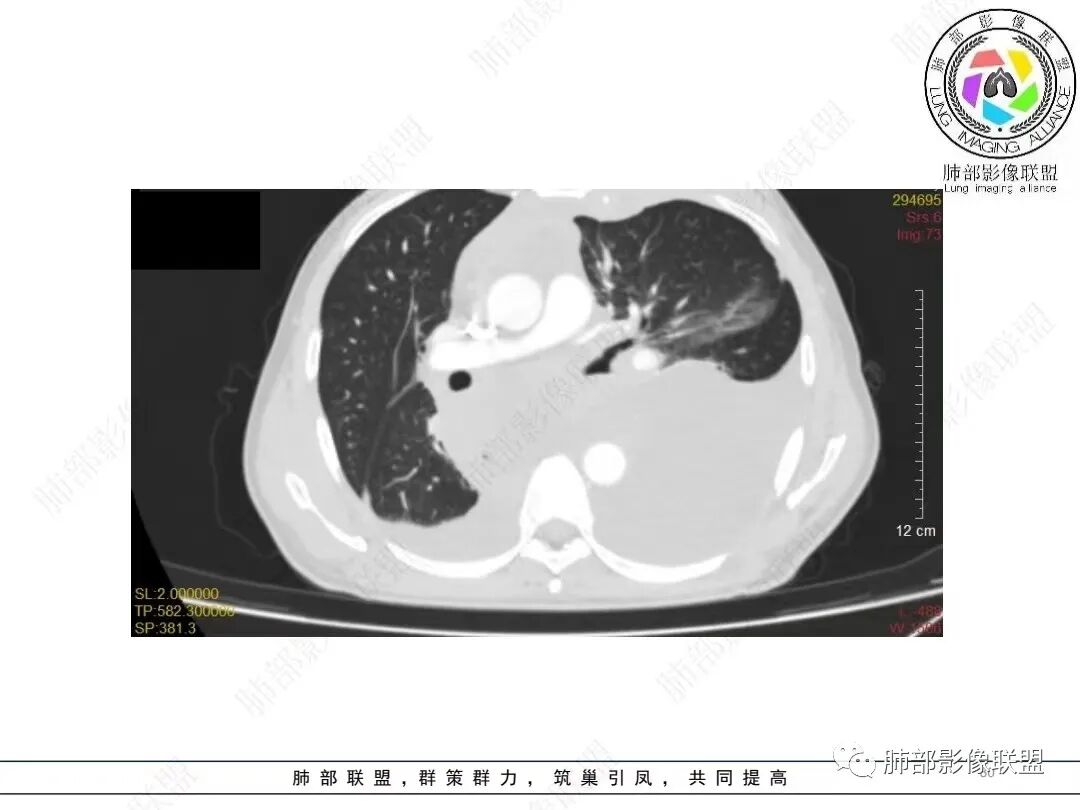

目前的图:主要是胸部的病灶。胸膜弥漫斑块状增厚。强化明显,内部血管漂浮。前纵隔部分病灶强化偏低。

累及多个腔隙、特别是后纵隔、胸膜为主

我把这个征象给忽略了,感觉很奇怪的病例。事后诸葛亮一下。这里的弥漫性,连续性增厚,有点特异性,还是要考虑到恶性间皮瘤的可能性的。胸膜转移瘤,不会这么连续性的不规则增厚。食管管腔是存在的,而且是推移明显,食管来源的话这种表现的最常见就是平滑肌瘤,不太符合。另外用小细胞解释腹腔病变感觉有点牵强,而且食管推移这么的明显,用淋巴瘤不好解释左心膈脚的这个软组织。没公布答案的时候,我一直在拿不准它到底是个啥。

2.影像学特点:病变范围相当广泛,多发块状影累及纵隔、胸膜、前胸壁(胸大肌下)、前上腹壁等。胸膜弥漫性斑状增厚为主,明显强化,纵隔旁椭圆形块影较密实,沿胸膜分布趋势,未见支气管等结构进入。后纵隔块影较大,占位效应明显,肺静脉受累狭窄。双侧胸腔积液。

3.总结: 多发块影,边界不清,占位效应明显,通常符合恶性肿瘤。两肺未见明确支气管相关块影或结节影,支气管肺癌的判断似乎缺乏立足点,前纵隔、胸膜以及胸腹壁块影也不是支气管肺癌的常见转移途径。

非上皮来源的恶性间叶组织肿瘤应当纳入视线,广泛性侵犯,区域性转移等等,梭形细胞瘤、原始神经外胚叶肿瘤(PNET)、恶性胸膜间皮瘤等等,如果病灶有区域分布优势,如本例的左侧胸膜改变,可以想到胸膜间皮瘤可能性。